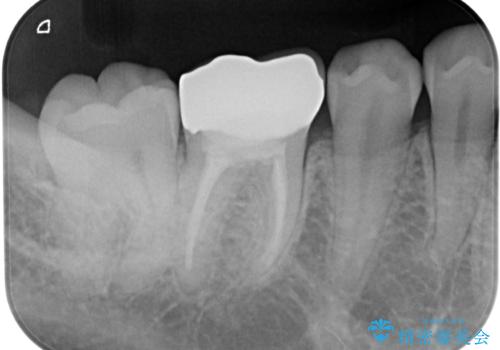

- 銀歯を白くしたいとのことで来院された患者様です。

拡大鏡視野下にて、銀歯を外して、虫歯を除去して、オールセラミッククラウンに適した形に削りました。

型どりはシリコーン印象材にて型どりしています。

見た目、噛み合わせともに満足していただけました。

歯質と被せ物(クラウン)の境目も適合の良いものができました。